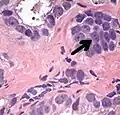

Intraductal carcinoma of the prostate with very patchy basal cells identified by immunohistochemistry. At least some of the glands lacking basal cell immunoreactivity represent intraductal rather than invasive carcinoma (a haematoxylin and eosin, b CK 5/6)[19]